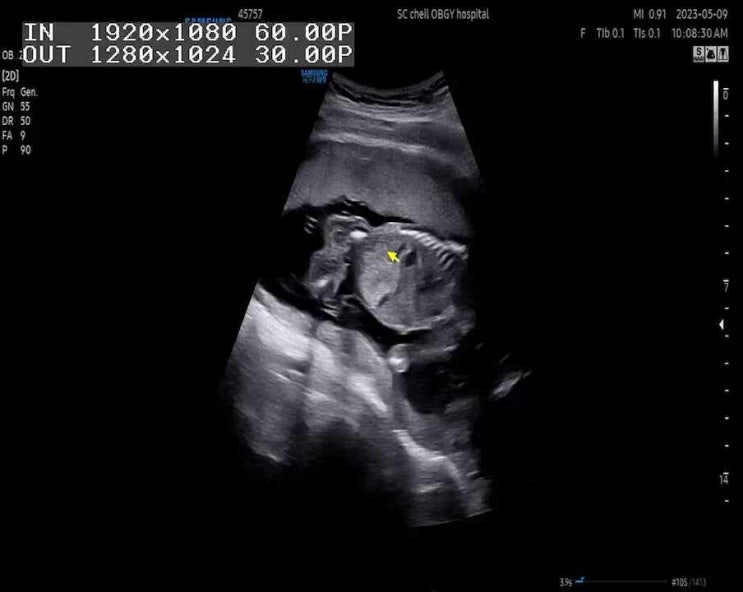

22주 1일: 정밀초음파, 태아 심장소리, 무게, 태아 크기

한달만에 띵동이를 만나러 가는 길 오전 10시에 예약을 하고 조금 일찍 방문 했다 오늘은 정밀초음파를 보...